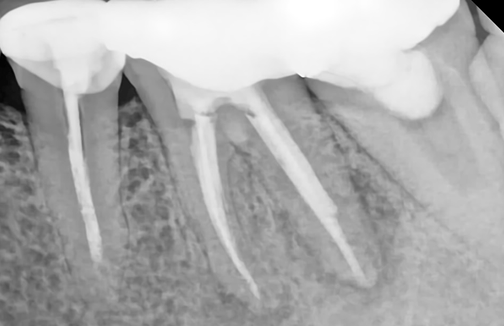

자연치아를 살리는 골든타임,

바로 지금입니다.

자연치아 하나의 가치는 3천만 원 이상,

빠르게 조치할수록 살릴 수 있는 확률은 올라갑니다.